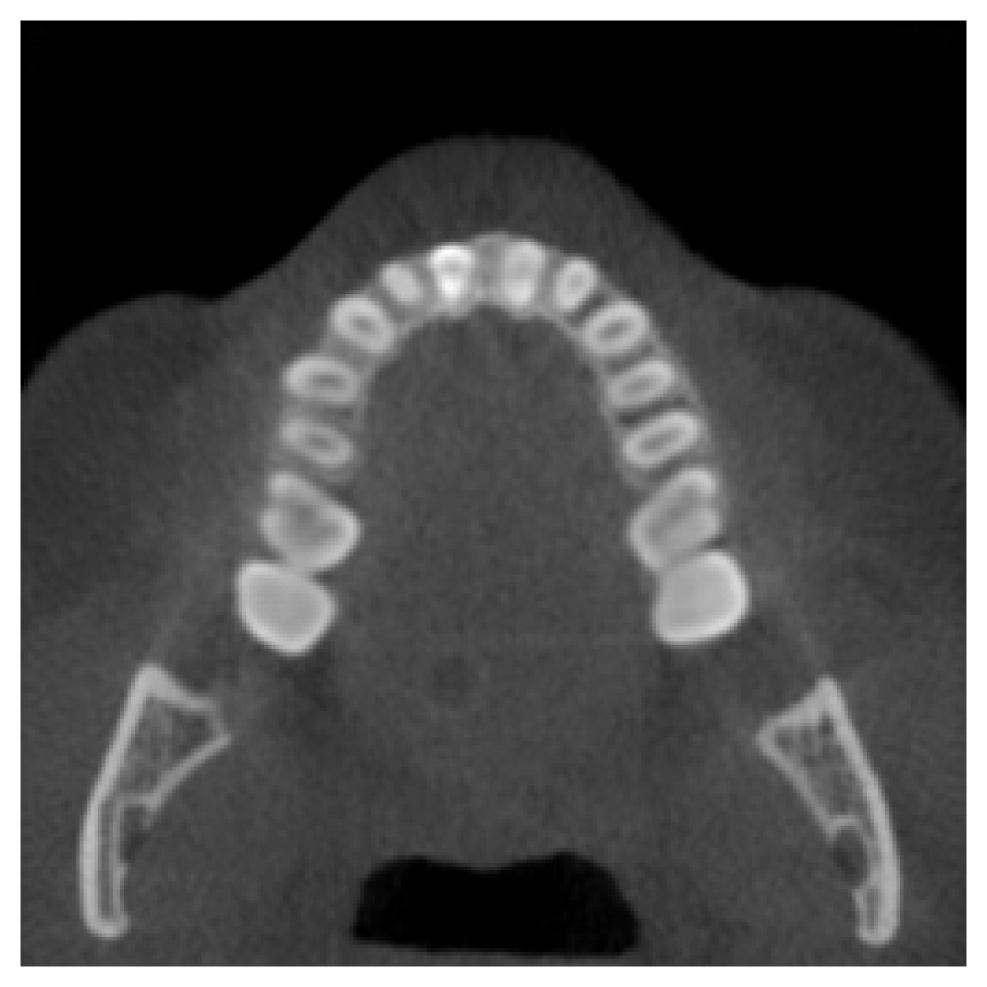

Full Dental Synthesis.

As a final experiment, we evaluate the model’s performance on generating a complete dentition in scans with no teeth present. This assesses the model’s ability to synthesize anatomically plausible full dental structures from the conditioning vector. Fig. 3 presents qualitative results comparing the generated samples to real scans with complete dentition. The visual comparison demonstrates a strong alignment between the real and synthetic inpainted regions. Quantitative evaluation supports this observation, with an average SSIM of 0.9123 and an average PSNR of 18.35 computed over the inpainted areas, despite the model not having seen the test samples during training.

Refer to caption

(a) Real Scan 1

(b) Synthetic Scan 1

(c) Real Scan 2

(d) Synthetic Scan 2

Figure 3: Qualitative comparison between generated CBCT scans and their corresponding real scans with complete dentition.